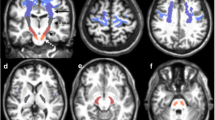

A ROI approach was used to measure FA and MD. A neuroradiologist (K.K.) with 6 years experience and blinded to the subject’s characteristics at the time of image analysis placed the 22-mm2 round ROI over the pons, the center of the bilateral MCP, and the posterior limb of the bilateral internal capsule on the FA and MD maps. The pons was divided into nine segments: ventral, central and dorsal rows in an AP direction, and the right, middle and left sides in the transverse direction (Fig. 1). Half-sized ROIs were used in patients with marked atrophy of the pons and MCP to avoid contamination by cerebrospinal fluid. The inferior and superior cerebellar peduncles were so small that no attempt was made to measure the FA and MD of these structures.

ROIs used in the data analysis. a, c Color-coded FA maps on which regions of high anisotropy are shown in yellow and red, and regions of low anisotropy are shown in blue at the level of the pons (a) and the internal capsule (c). b, d Color-coded MD maps on which regions of high diffusivity are shown in yellow and red, and regions of low diffusivity are shown in blue at the level of the pons (b) and the internal capsule (d). The numbered circles show the regions of interest: 1 right, 2 middle, 3 left in the ventral row of the pons; 4 right, 5 middle, 6 left in the central row of the pons; 7 right, 8 middle, 9 left in the dorsal row of the pons; 10 right, 11 left in the MCP; 12 right, 13 left in the posterior limbs of the internal capsule